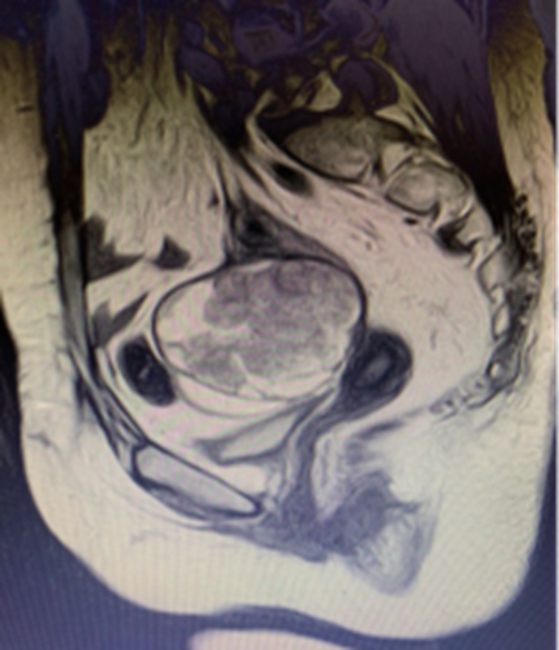

(经详细检查确定,童女士腹腔粘连较重,肿瘤位于盆底,直径10cm大小,与周围肠管,膀胱,输尿管,血管,神经紧密相连,广泛粘连。)

手术历时12个小时,妇瘤病院胡艳副主任医师携同普外科张吉成主任医师,成功完成了高度复杂的膜间隙手术,及部分乙状结肠切除和盆腔肿块切除,最大限度的保留了正常脏器组织功能,患者术后没有出现吻合口瘘、阴道膀胱瘘、阴道直肠瘘等并发症。目前董女士正在术后恢复中,状态良好。

(手术切除透明细胞癌实体瘤大小约8*8.5*9cm,被覆部分乙状结肠肠管,结肠带,脂肪组织,残端宫颈,盆底周围软组织、血管等。)